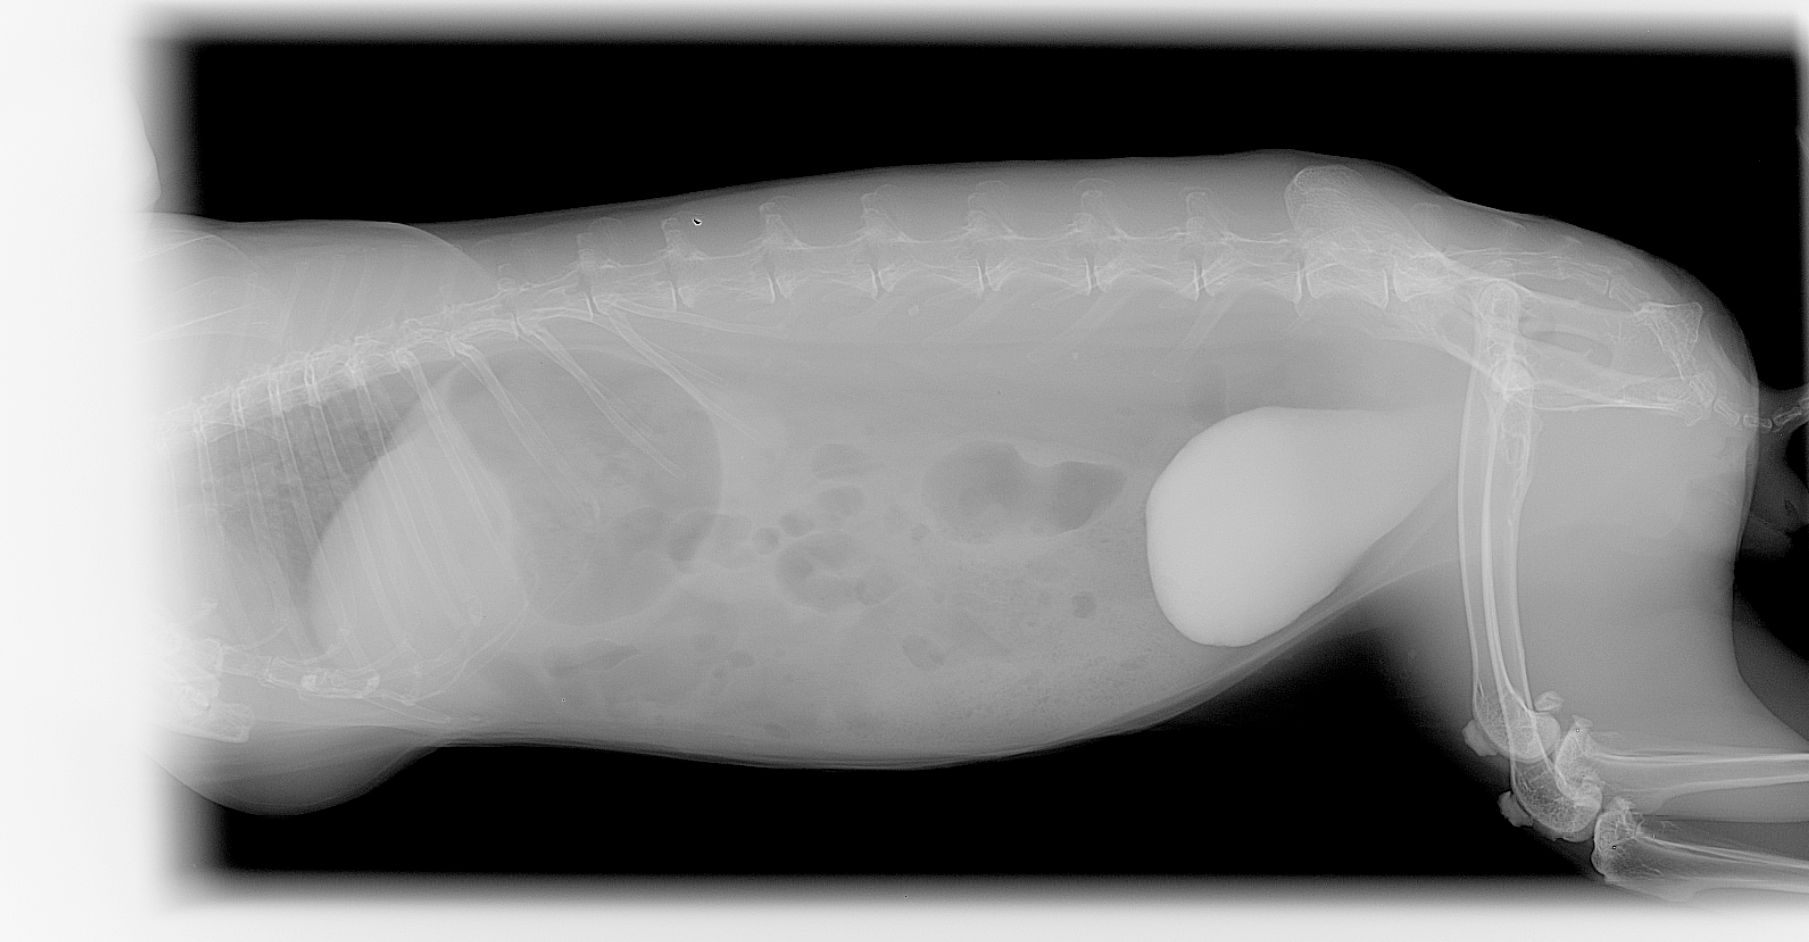

Les calculs urinaires dans la vessie sont courants chez le lapin et le cobaye et ils sont également observés plus rarement chez les chinchillas. Ils peuvent être particulièrement délétères et causer une douleur intense lors de l'émission des urines et la présence de sang dans les urines. En cas d'obstruction urinaire (impossibilité d'évacuation des urines), il s'agit d'une urgence vitale absolue pour le lapin et les rongeurs.

Le diagnostic se fait par radiographie mais une échographie et une prise de sang sont recommandés pour exclure la présence d'autres calculs au niveau des uretères et des reins et aussi pour vérifier l'absence d'insuffisance rénale. Le traitement est quasiment toujours chirurgical, certains cas particulier peuvent être traité par endoscopie ou par traitement médical.

Calcul vésical

Le diagnostic est relativement aisé par radiographie. Cependant, toutes les sabloses ne sont pas nécessairement pathologiques. Un bilan complet associant prise de sang et échographie est recommandé. Le traitement passe par une amélioration de l'hydratation et des rectifications alimentaires. Cette sablose peut prédisposer aux calculs vésicaux, urétéraux ou rénaux.

La sablose urinaire est courante chez le lapin ou le cobaye. Les causes sont généralement liées à un défaut d'hydratation, un excès de calcium alimentaire ou un défaut de mobilité (sédentarité). La présence de sable urinaire en grande quantité peut être irritant et provoquer des difficultés à uriner, de la malpropreté, des cystites ou du sang dans les urines.